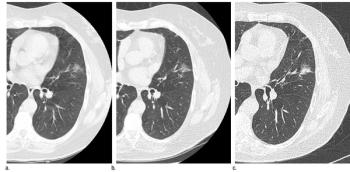

Low-dose CT observation of nonsolid lung nodules is safe.